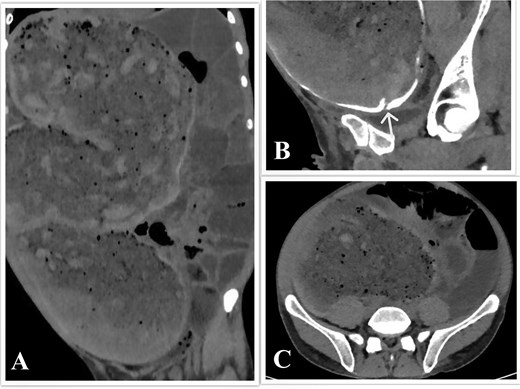

Computed tomography (CT) of the abdomen and pelvis with rectal contrast revealed significant fecal loading, colonic dilatation reaching 11.5 cm at the mid-sigmoid level (Fig. 1), a 2 cm stricture 25 cm from the anal verge (Fig. 1B), and small bowel dilatation.

CT scan of the abdomen and pelvis. (A) Coronal view showing the megacolon and small bowel dilatation. (B) Sagittal view showing the sigmoid stricture, with the arrowhead pointing toward it. (C) Axial view showing colon dilatation at the mid-sigmoid level.

Imaging, particularly CT or magnetic resonance imaging, is essential to rule out obstruction [2], measure the colonic diameter, and evaluate for complications such as perforation [9]. A sigmoid diameter > 10 cm is diagnostic [9]; our patient’s reached 11.5 cm. Endoscopy, though typically avoided for perforation risk [9], can aid in diagnosis, biopsy [2], and decompression [14], as in this case.